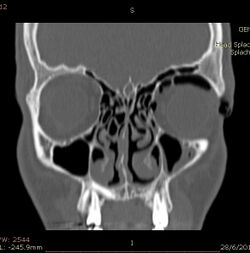

CT scan taken from the transverse plane demonstrating orbital emphysema.[39]

CT scan taken from the coronal plane demonstrating orbital emphysema.[39]

Computed tomography is effective and sensitive in the diagnosis of orbital emphysema,[3][37] as it can confirm the anatomical location and size of air, bony defects, indentation of the eyeball, and the condition of the optic nerve, as well as the presence of any extraocular muscle entrapment and herniation of preorbital fat into the sinus cavities.[3][15][38] The location of the orbital emphysema is present near the site of the fracture.[1][3] The scans are usually taken along the transverse plane. Transverse images allow the evaluation of fractures in medial and lateral orbital walls. By reformatting these transverse images or taking coronal images, the examination of orbital floor and roof is permitted. Helical scanning is preferred as it has a lower imaging time and radiation dose comparing to conventional scanning, especially when reforming transverse helical scans into coronal images.[3] The staging of orbital emphysema can then be determined with visual acuity examination and ophthalmoscopy.[6] A disadvantage of using a CT scan is that when detecting air after orbital trauma, the presence of a wooden foreign object can give a false positive result of orbital emphysema. The wooden object can mimic the presence of orbital emphysema. Therefore, patients’ medical history is crucial in making the correct diagnosis.[3]